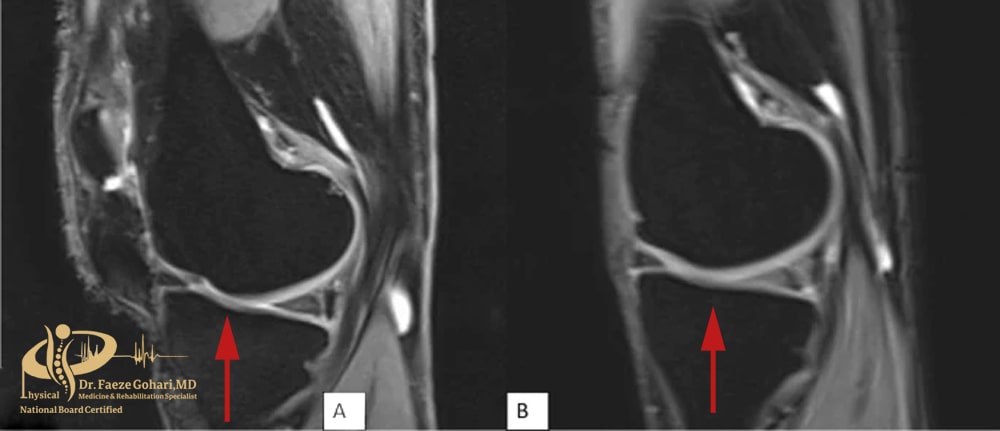

تصویر A قبل از پی ار پی – تصویر B یکسال پس از پی ار پی (کاهش قابلتوجه آسیب غضروفی در بیمار ۶۷ساله)